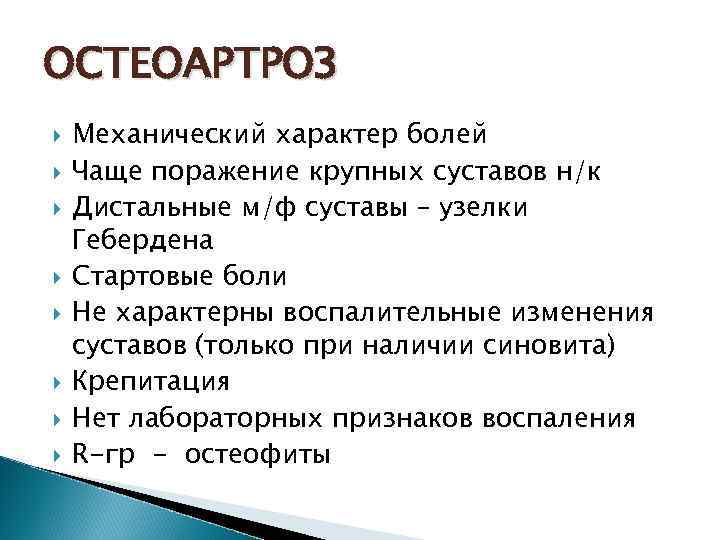

ОСТЕОАРТРОЗ Механический характер болей Чаще поражение крупных суставов н/к Дистальные м/ф суставы – узелки Гебердена Стартовые боли Не характерны воспалительные изменения суставов (только при наличии синовита) Крепитация Нет лабораторных признаков воспаления R-гр - остеофиты